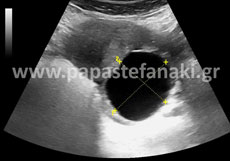

Υπέρηχοι Κάτω Κοιλίας

Η προετοιμασία του ασθενούς είναι απαραίτητη.

Έτσι 2 ώρες πριν την εξέταση πρέπει να πιείτε 5-6 ποτήρια υγρών (νερό, χυμό μη ανθρακούχο κλπ) ώστε να γεμίσει η ουροδόχος κύστη (άρα δεν πρέπει να ουρήσετε πριν την εξέταση).

Δεν πρέπει να έχει προηγηθεί την ίδια ημέρα γαστροσκόπηση, ορθοσκόπηση, εξέταση στομάχου ή εντέρου.